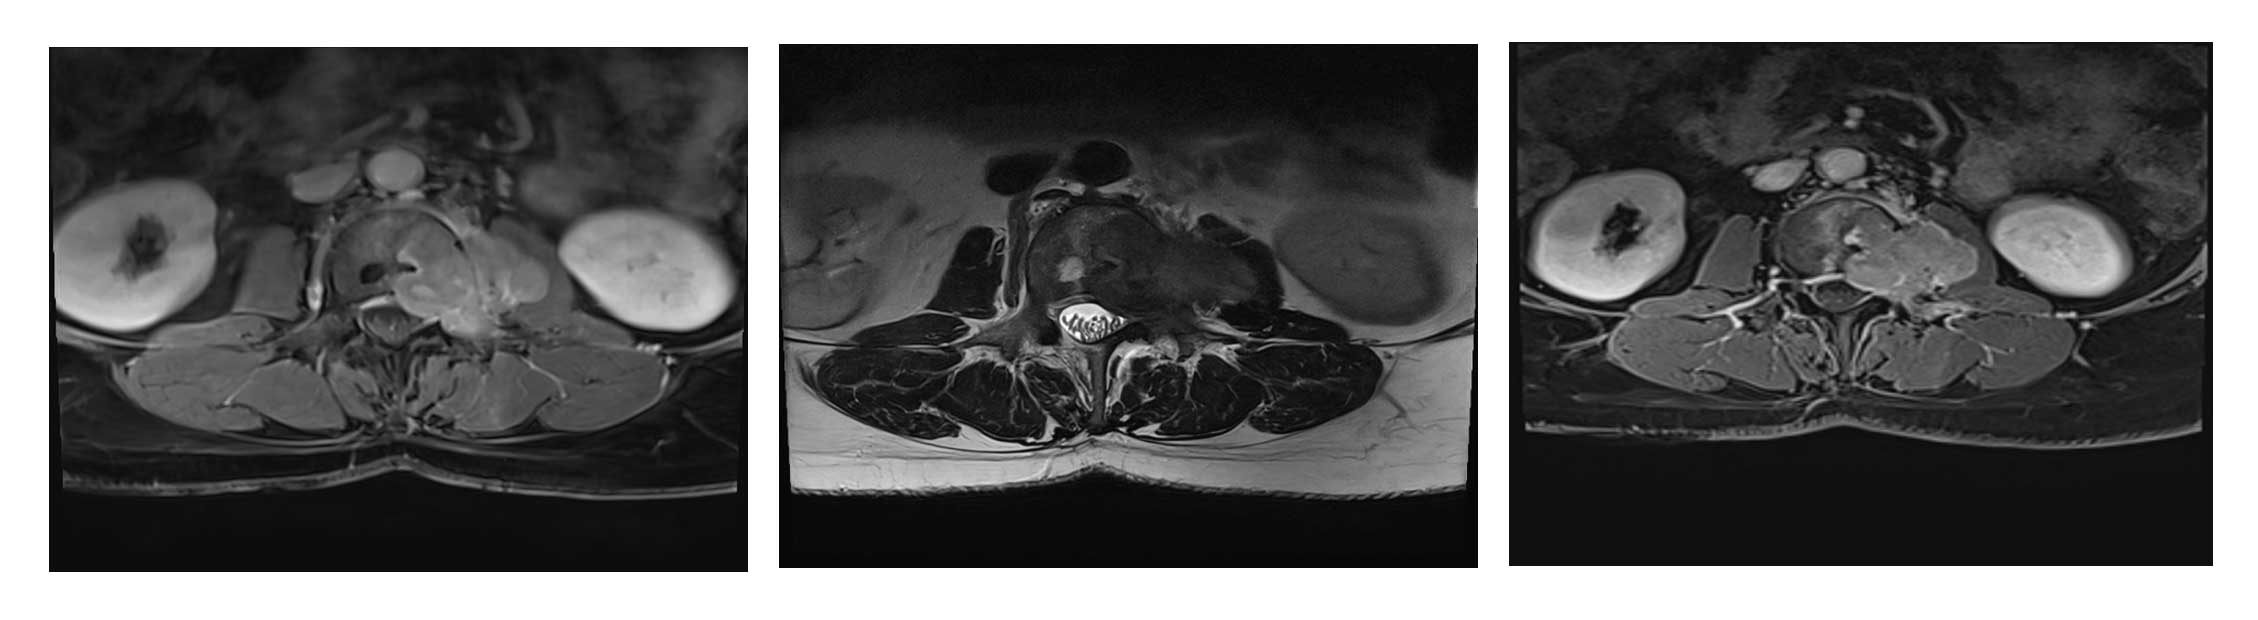

Ameliyat Öncesi: MR’da kemiğin dışına taşmış, kasın içine girmiş ve sinir basısına neden olan büyükçe tümör dokusu görülmekte.